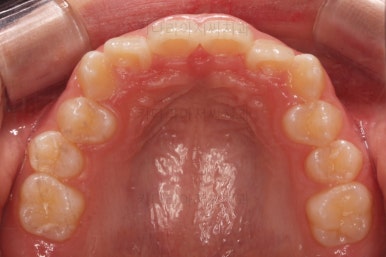

초진 시 입안의 모습입니다.

전반적으로 치열이 삐뚤삐뚤하고요.

우선 윗니에만 교정장치를 부착했습니다.

성장치료라더니 교정치료? 하실 수 있지만 윗니를 가지런하게 해준 이유는 아래턱을 앞으로 성장시켜줄려니 윗니 앞니가 옥니처럼 가로막고 있어서 아래턱이 앞으로 나올래야 나올 수 없는 상황이었어요.

그래서 앞니의 각도를 먼저 개선해주기로 했죠.

앞니 각도가 매우 좋아졌고요.(옥니 개선) 위 아래 앞니가 덮는 정도도 개선되었어요.(과개교합, 딥바이트)